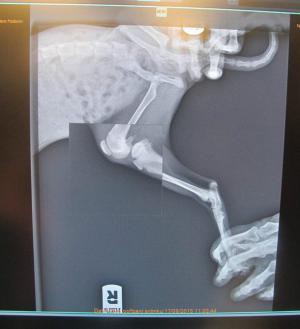

Kočičce jsme dali jméno podle její nálezkyně - Darinka. Darinka má přetrhané vazy v koleně na zadní nožce. Vypadá to, že ji někdo záměrně ublížil. U přední nohy můžete na rentgenu vidět brok, takže po ní i stříleli ze vzduchovky.

Ve čtvrtek jedeme do Uherského Hradiště na operaci, která bude stát odhadem asi deset tisíc korun.

Dnešní faktura je 7 921,- Kč a je splatná do 3.9.2015. Příští týden pojedeme na kontrolu.